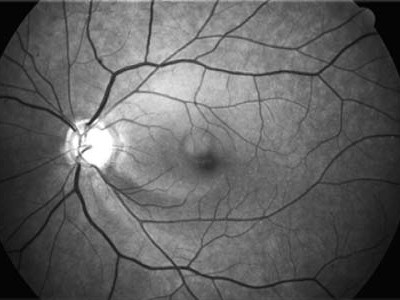

Glaukom - zobrazovací metody

Současné zobrazovací metody glaukomu považujeme za velmi přínosné pro stanovení diagnózy glaukomu a sledování vývoje onemocnění v čase. Těmito metodami sledujeme objektivně projevy glaukomové neuropatie včetně její progrese.